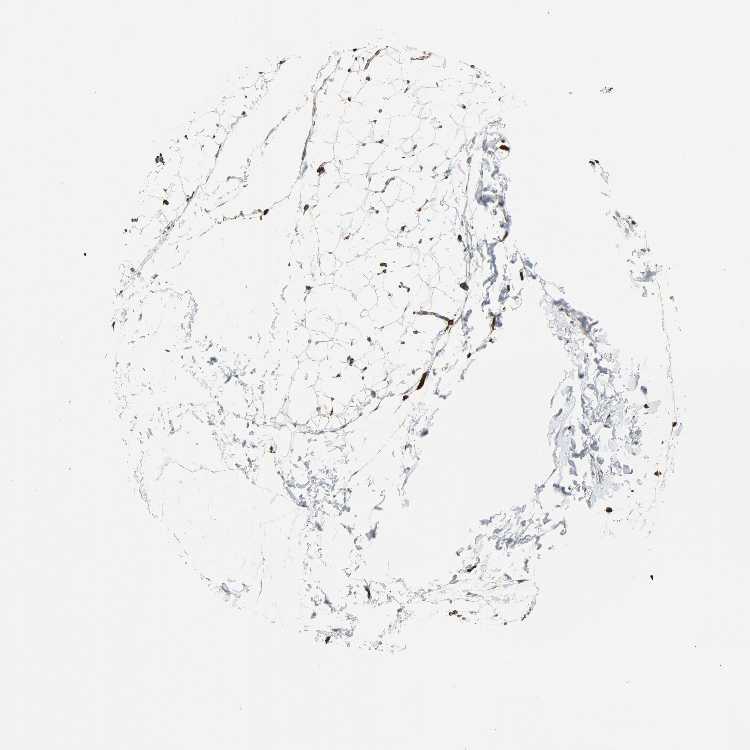

ADIPOSE TISSUE - Antibody stainingi

Antibody staining in the annotated cell types in the current human tissue is reported as not detected, low, medium, or high, based on conventional immunohistochemistry profiling in selected tissues. This score is based on the combination of the staining intensity and fraction of stained cells.

Each image is clickable and will lead to virtual microscopy that enables deeper exploration of all samples and also displays staining intensity scores, fraction scores and subcellular localization as well as patient and tissue information for each sample.

Antibody HPA005724Antibody CAB004612

Adipocytes LowMedium